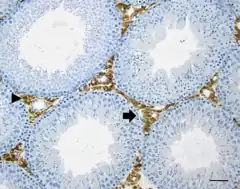

![]() Células de Leydig en marrón (flecha). Túbulos en celeste. | ||

Las células de Leydig o células intersticiales del testículo[1] son las células secretoras endócrinas encargadas de secretar cerca del 90% de la hormona masculina (testosterona), están localizadas en el compartimento intersticial entre los túbulos seminíferos del testículo.

Las células de Leydig están ubicadas en el espacio entre los túbulos seminíferos llamado compartimento intersticial, se encuentran rodeadas por el tejido conjuntivo laxo, con microvasculatura. Por su función endócrina, corresponden al parénquima ya que secrecretan la hormona masculina testosterona.[2][3]

Con el microscopio óptico, las células intersticiales secretoras de Leydig, tienen forma redondeada o poligonal con un diámetro de 15-20 micrómetros (μm).

Se ven agrupamientos de estas células secretoras dentro del intersticio intertubular, en estrecha cercanía de los capilares sanguíneos.[3]